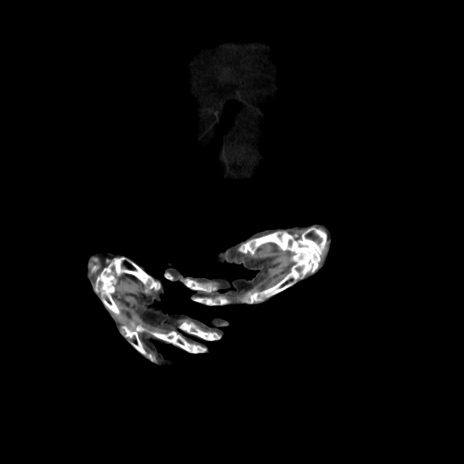

横断像